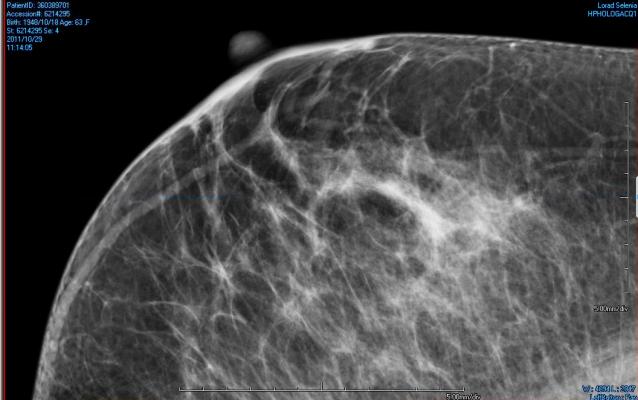

February 18, 2015 — State legislatures in Georgia and Kentucky both introduced bills last week that would require physicians to notify women about dense breast tissue and its implications for detection of breast cancer.

The Georgia bill (HB269) would require notifications to patients about breast density in all mammography, regardless of whether dense breast tissue was indicated in the results or not. Information is to be drawn from the American College of Radiology’s Breast Imaging Reporting and Data System (ACR’s BI-RADS)

“Dense breast tissue may hide small abnormalities. If your mammogram indicates that you have dense breast tissue, you may benefit from supplementary screening tests, including a breast ultrasound screening, a breast MRI examination, or both, depending on your individual risk factors. A report of your mammography results, including information about your breast density, has been sent to your physician’s office. If you have any questions or concerns about this report, you should contact your physician.”